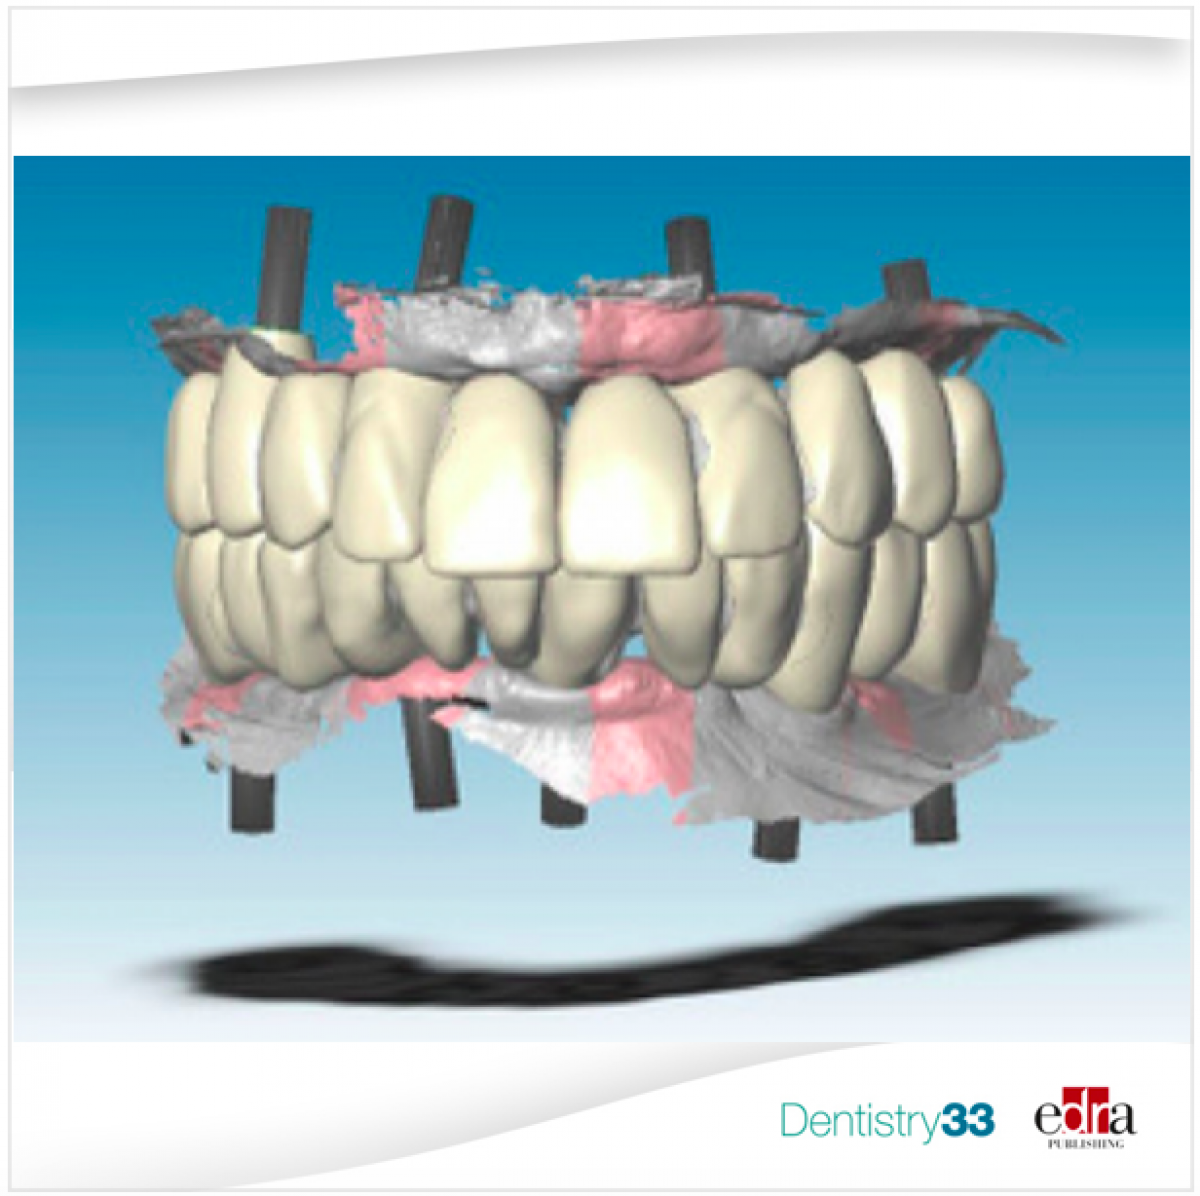

The STL4 file, which at this point represented the virtual master model, was used to create two stereolithographic master models with the implant analogs. Also starting from the STL4 file, two aluminum bars (one for the upper and one for the lower one) with integrated implant connections (Figure 4) have been designed and made to CAD / CAM.

The digital design procedure was facilitated by the presence of the virtual wax-up of the final prosthesis (based on the form of functionalized temporaries) on STL4. This allowed the technician to draw the anchoring pins of the substructure based on the position of the teeth in the prostheses (Fig. 8).